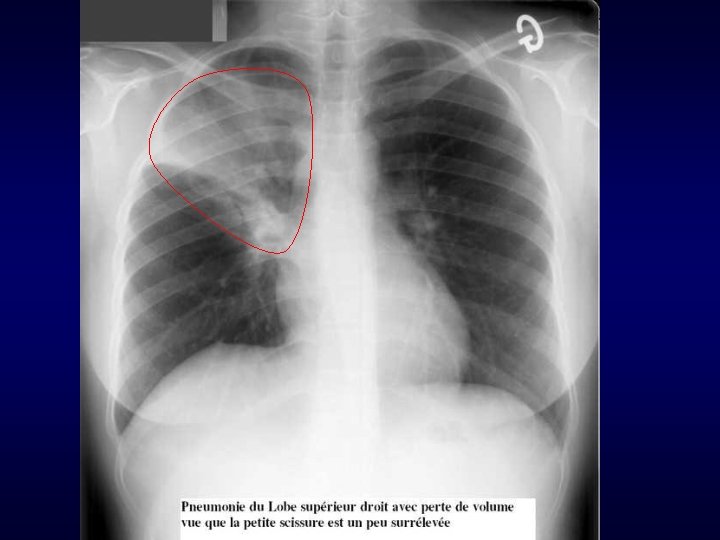

Pneumopathies Examens complémentaires Radiographie de thorax Opacité en foyer (Pneumopathie systématisée franche lobaire aiguë) ou Pneumopathie +/- interstitielle ou Abcès du poumon +/- Pleurésie